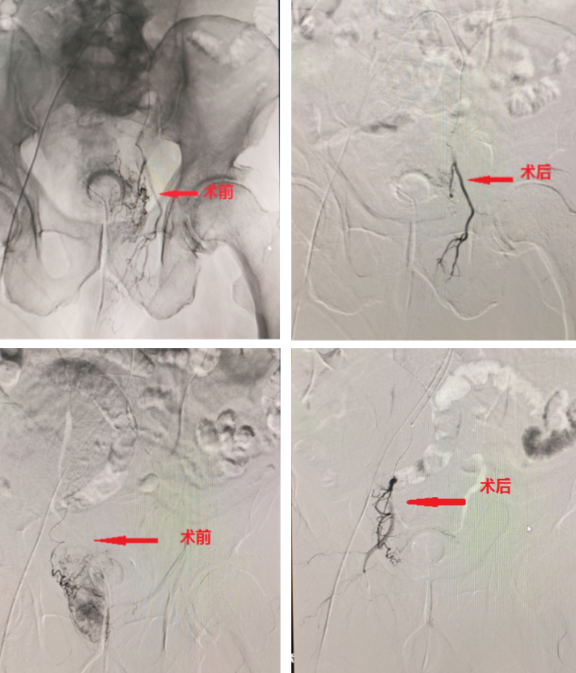

2025年4月9日13:20,我院急诊科接诊1例血尿患者,该患者77岁高龄,既往前列腺增生病史10余年,12小时前因小便困难留置尿管后出血,导尿管阻塞。经我院介入科、泌尿外科、急诊科多学科MDT会诊后,建议患者行前列腺供血动脉栓塞治疗。经患者及家属同意后急诊手术,术后患者未再出血。

前列腺增生介入栓塞术应运而生!作为国际前沿的微创介入技术,它通过阻断前列腺供血动脉,使增生腺体自然萎缩,从源头解决问题,创伤小、恢复快、并发症少,为患者提供更优选择!

2. 精准安全:DSA影像引导下精准栓塞前列腺供血动脉,不损伤周围组织,保留男性功能。